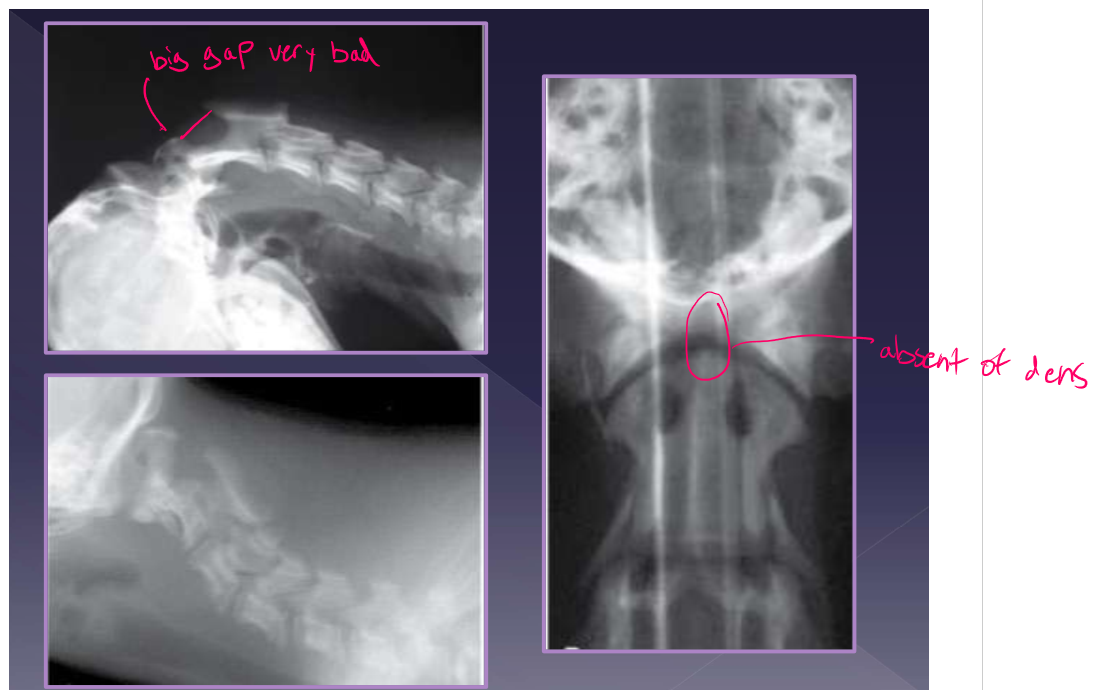

Atlantoaxial instability

abnormalities

aplasia of the dens - 46%

hypoplasia of the dens - 34%

dorsal dens angulation

separation of the dens

ligamentous instability

up to 24% of dogs with A-A instability have an normal dens

diagnosis for atlantoaxial instability

physical examination: Do not flex the neck! makes C2 go dorsally and makes pain worse in flexion of neck

radiographs

increased distance between dorsal arch of C1 and dorsal spinous process of C2